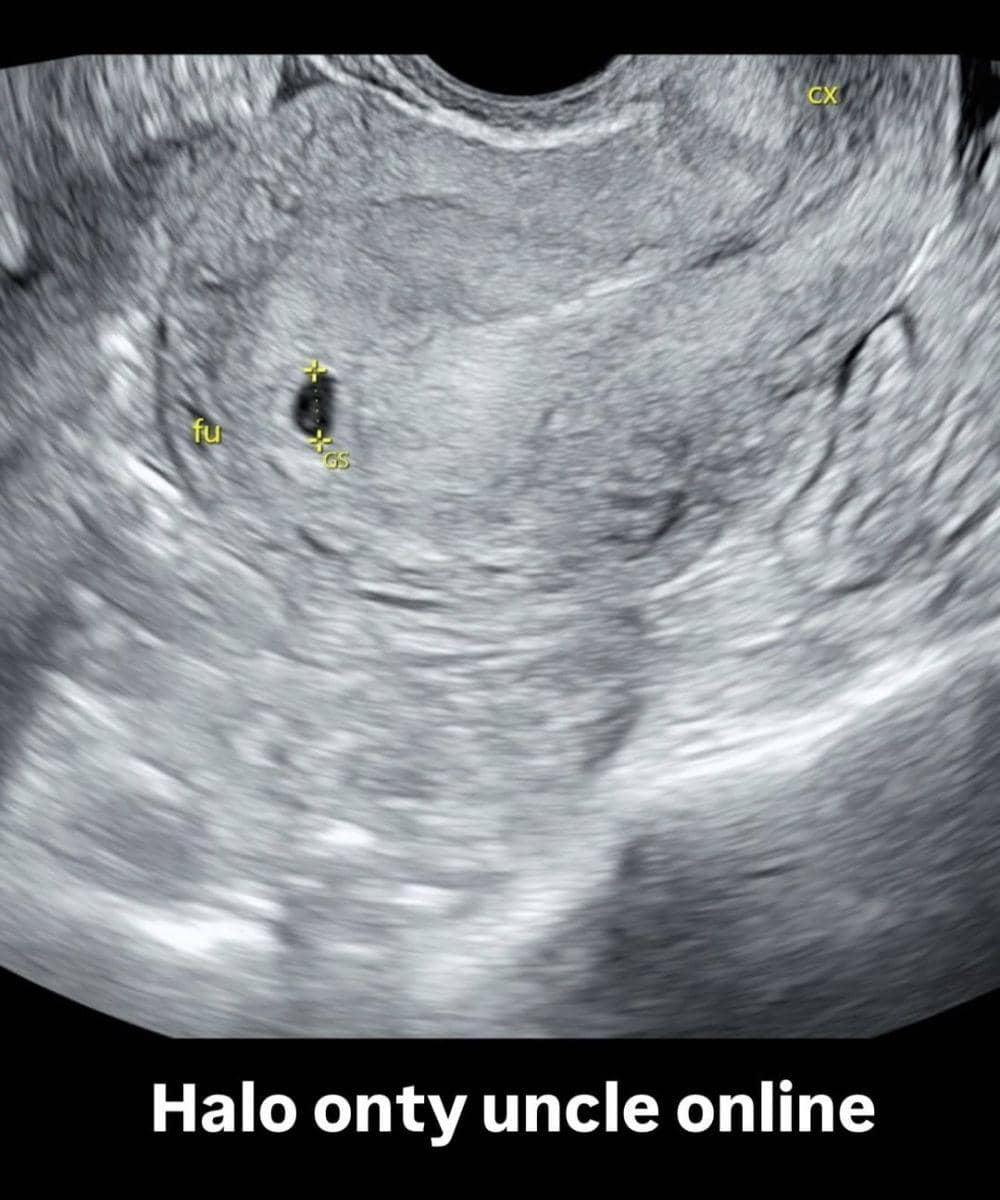

Selain mengumumkan hamil dan membagikan foto test pack positif, Amanda Manopo juga mengunggah foto USG. Foto itu diunggahnya di Instagram Story sekaligus tulisan "halo onty uncle online".

Dari foto USG tersebut terlihat kantung kehamilan (gestational sac/GS) dan sudah tampak bakal embrio yang sangat kecil. Biasanya tampilan USG seperti ini ditemukan pada usia kehamilan sekitar 5–6 minggu (awal trimester pertama).

Amanda Manopo tidak mengunggah foto USG-nya secara lengkap. Pasalnya tidak ada informasi terkait HPHT (Hari Pertama Haid Terakhir) dan ukuran CRL (crown-rump length) jika embrio sudah terlihat jelas.